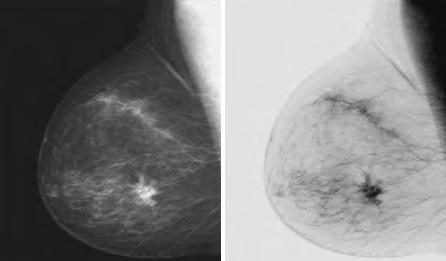

这种变换适用于增强嵌入图像暗区的白色或灰色细节。例如,在数字X线照片中分析身体结构组织。

图片来源:Slideshare.net